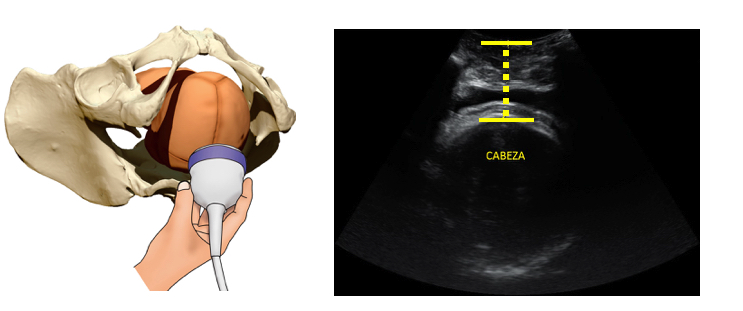

Ecografía obstétrica intraparto para matronas

Duración: 2h

Plazas: 15 por edición

- CONTENIDOS

- Principios de ecografía intraparto

- Cefálica vs podálica

- Cortes básicos de ecografía intraparto

Ecografía obstétrica intraparto para obstetras

Estos talleres se realizan con la colaboración de la fundación imaterna.

Destinatarios: Obstetras

- Ecografía y dilatación cervical

- Distancia Cabeza periné

- Angulo de progresión